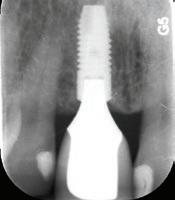

Depuis 1990, Implant Québec agit comme centre de référence pour la gestion des complications en implantologie, tant chirurgicales que prothétiques.

Ce qui nous distingue particulièrement, c’est notre savoir-faire en gestion des complications prothétiques et chirurgicales, un domaine souvent complexe et exigeant sur le plan clinique.

Ce service est offert grâce à une équipe expérimentée capable d’intervenir dans les situations les plus délicates et à une vaste expertise acquise depuis plus de 30 ans dans le domaine.

Nous accompagnons les professionnels et leurs patients dans divers contextes, notamment :

Péri-implantite

Restauration problématique

Reprise de cas complexes

Grâce à notre expérience clinique approfondie, nous prenons en charge tous types de traitements implantaires, peu importe :

L’origine du cas

Le système d’implants utilisé

Qu’ils aient été réalisés ici ou ailleurs dans le monde